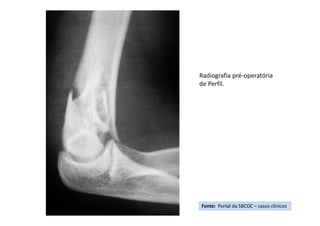

Radiografia pré-operatória

de Perfil.

Fonte: Portal da SBCOC – casos clínicos